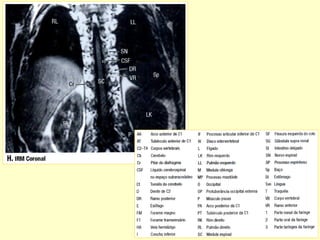

PADRÃO ‘ OURO’ PARA AVALIAR A

COLUNA POR MÉTODO DE IMAGEM

É A RESSONÂNCIA MAGNÉTICA.

Conteúdos intra-raquianos

RELAÇÕES ANATÔMICAS DA COLUNA